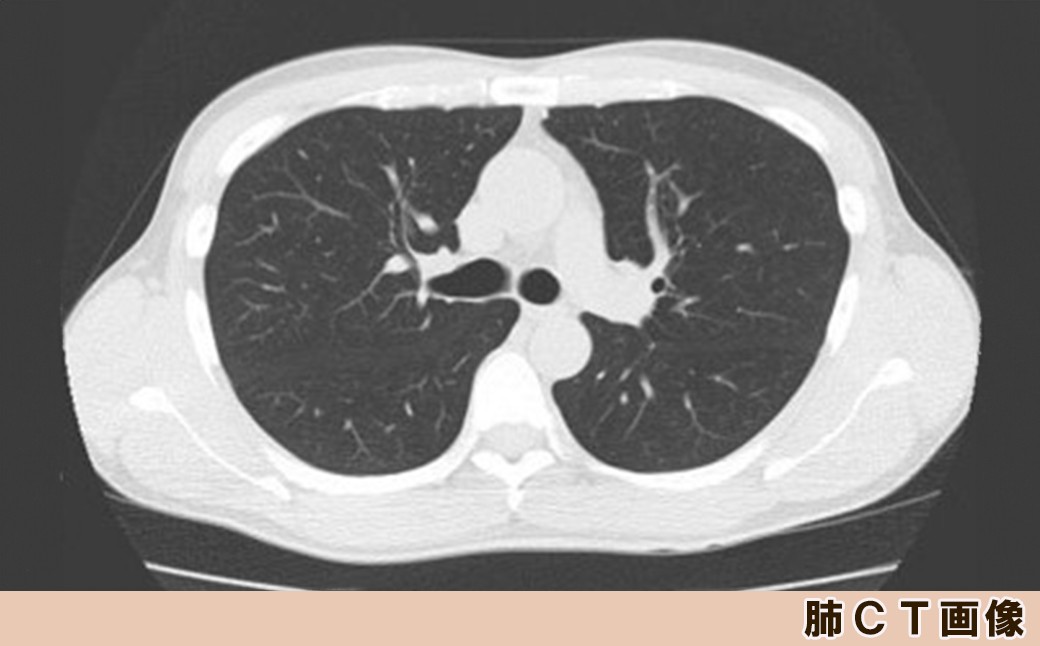

亀田クリニックにて肺CT検査(肺がん検診)をご受診いただけます。

胸部レントゲンでは検査特性上、早期の小さながんの発見は困難です。

肺のCTは胸部レントゲンより細かく体内の構造が確認できますので、肺がんの発見性能は胸部レントゲンより飛躍的に高くなります。

亀田クリニック健康管理センターのCT装置は2020年7月に新型機種となり、以前よりさらに被爆線量も少なく撮影することが可能となりました。

CTを使用した、詳しいレントゲン検査です。

体の中を断層したような画像で診断が可能です。胸部X線検査よりも詳細に体内を観察する事ができ、肺がんの発見精度が数段高くなります。